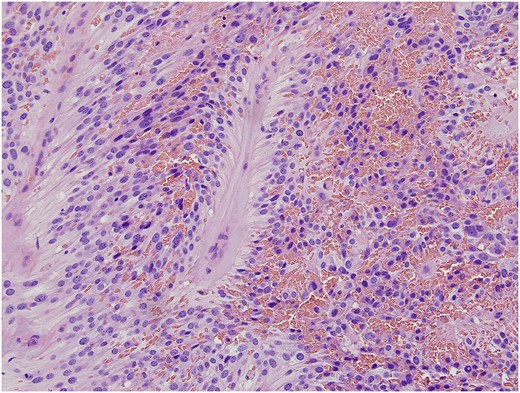

Final pathology revealed a moderately cellular neoplasm with cellular processes extending around blood vessels, formation of perivascular pseudorosettes, and areas of myxoid degeneration (Fig. 1). The neoplastic cells were strongly positive for glial fibrillary acidic protein (GFAP), CD-99, and CD-56, all of which supported the morphologic diagnosis of ependymoma (Fig. 2). The cephalad margin was positive for tumor. A follow up magnetic resonance (MR) of the pelvis and neuraxis was obtained, which demonstrated post-surgical changes and no evidence of persistent tumor (Fig. 3). After evaluation by neurosurgery, full neuro-axial imaging was performed and did not show any evidence of tumor or additional pathology. Excision of the positive cephalad margin and adjuvant chemotherapy or radiotherapy was not recommended. Long-term surveillance with frequent clinical examinations and pelvic MR was established.

Immunohistochemical analysis demonstrated diffuse and strong expression of CD99 (a), GFAP (glial fibrillary acidic protein) (b), and CD56 (c) in the neoplastic cells. They were negative for cytokeratin (AE1/AE3) which confirmed the morphologic diagnosis of ependymoma.